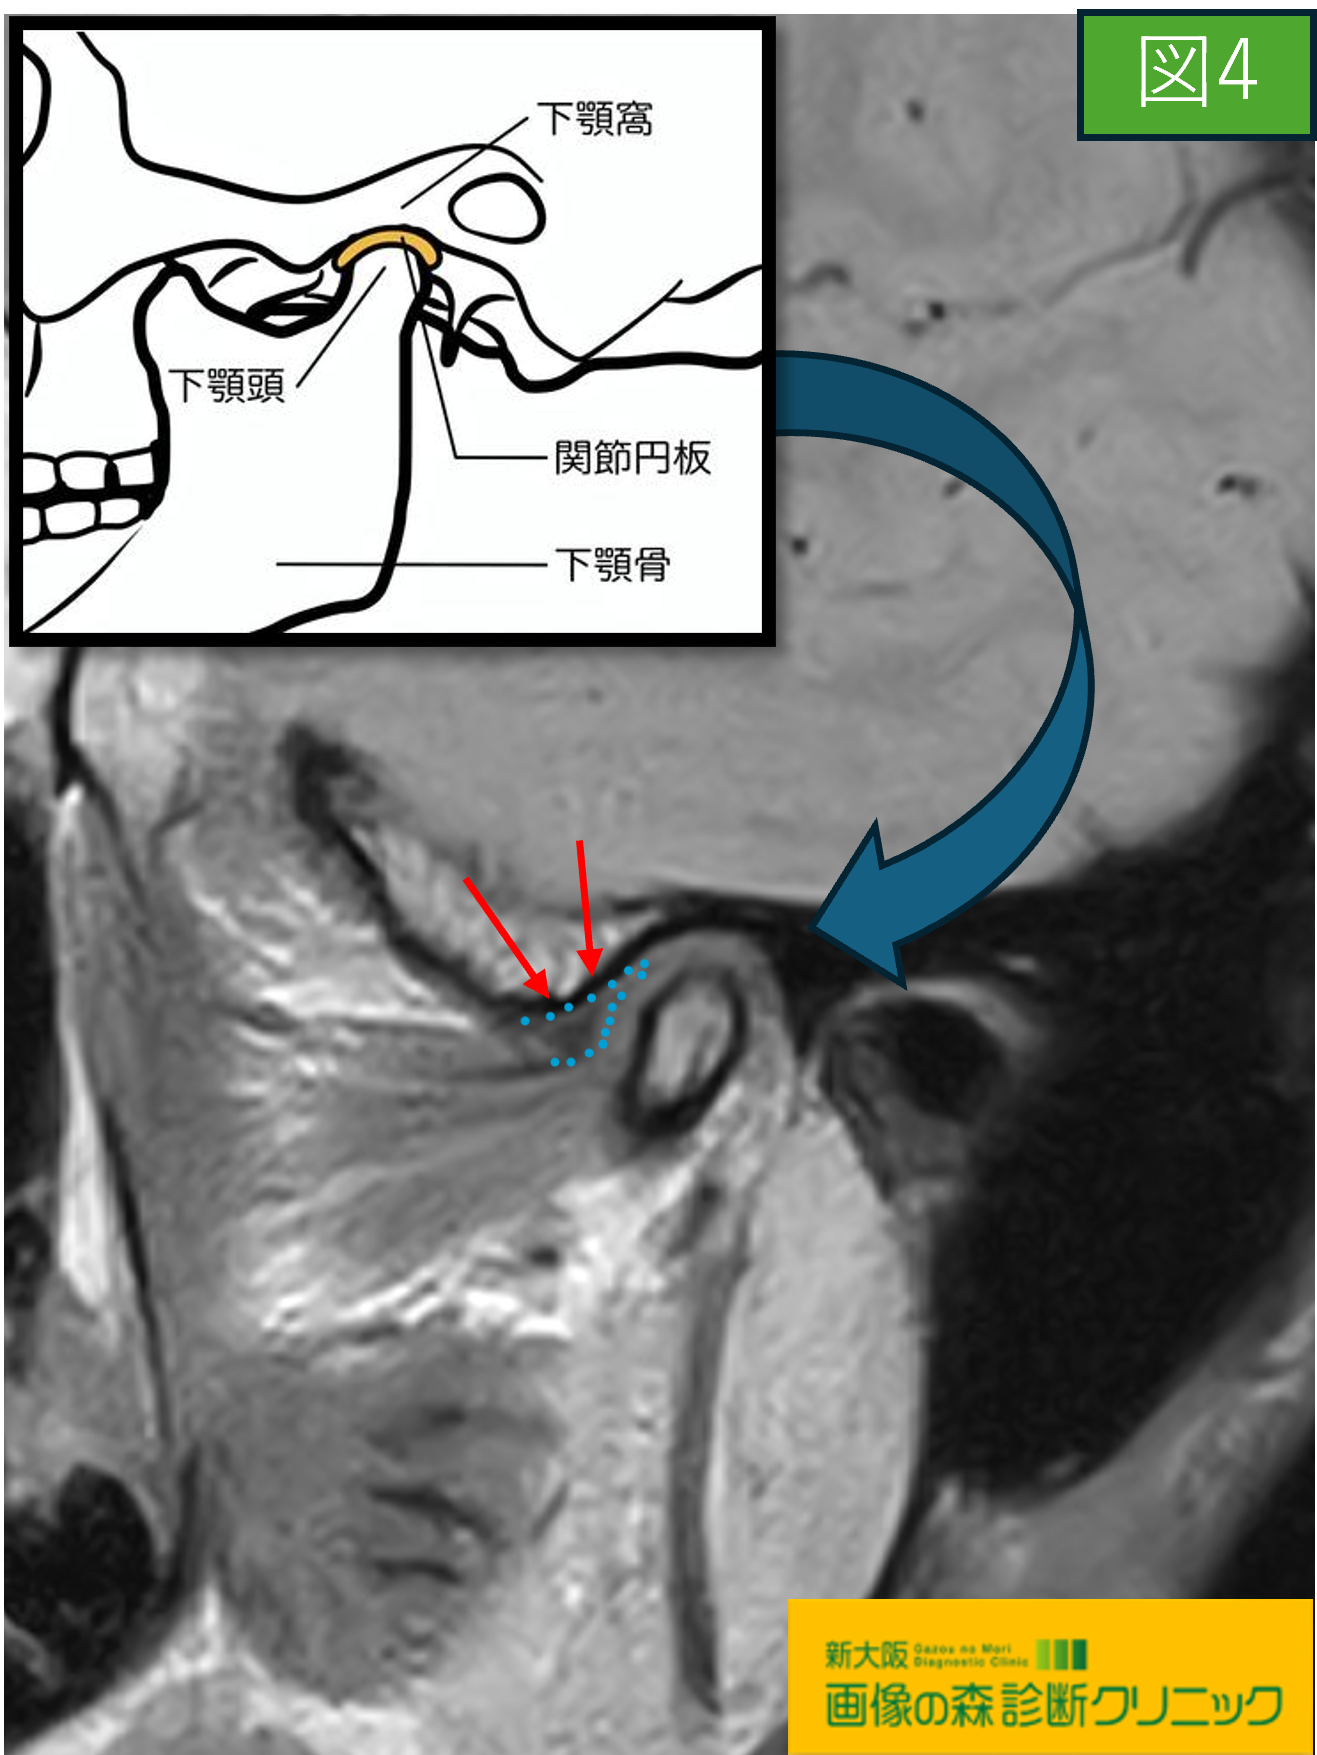

〇続けて図3・図4の画像は顎関節を横方向から観察しています

図3・図4の画像では主に関節円板に注目します。

また関節円板は、骨の間のクッションの役割があり

図4の症例画像では、関節円板(青い点線で囲っている黒色の

部分)は下顎頭より前に突き出しているのが観察出来ます。